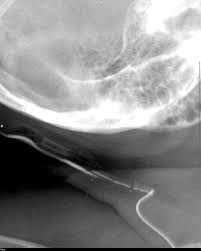

Vp shunt radiopaedia. Programmable cerebrospinal shunts are a type of ventriculoperitoneal shunt that can be set to different csf pressure settings. An example of a normal vp shunt series. The vp shunt on the right side of the neck seen best on the lateral neck skull and ap neck views appears discontinuous.

The shunt series in this patient demonstrate a vp shunt disconnection at the level of the lower neck best appreciated on the ap cervical spine view. Case contributed by radswiki. Indications departmental protocols will vary but the overall goal is to image the shunt in its entirety to assess.

An important series of films for checking the integrity of a in situ vp shunt. The shunt series is a set of radiographic images performed to assess the location and integrity of a ventriculoperitoneal shunt. Case contributed by dr adam eid ramsey.